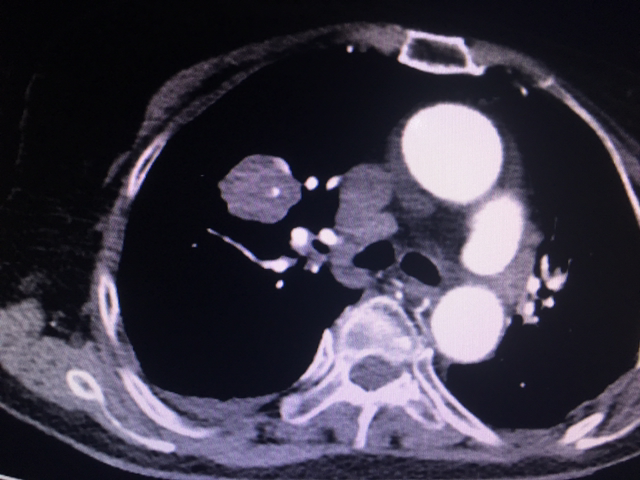

앗, 심장 뛰는 게 심상치 않다. 심증에 힘 실어줄 단서를 기대하며 흉부 CT까지 살핀다. 역시나 PTE (pulmonary thromboembolism, 폐동맥 색전증).

흉부 CT 상 PTE. 페동맥 색전증이 자명하다.